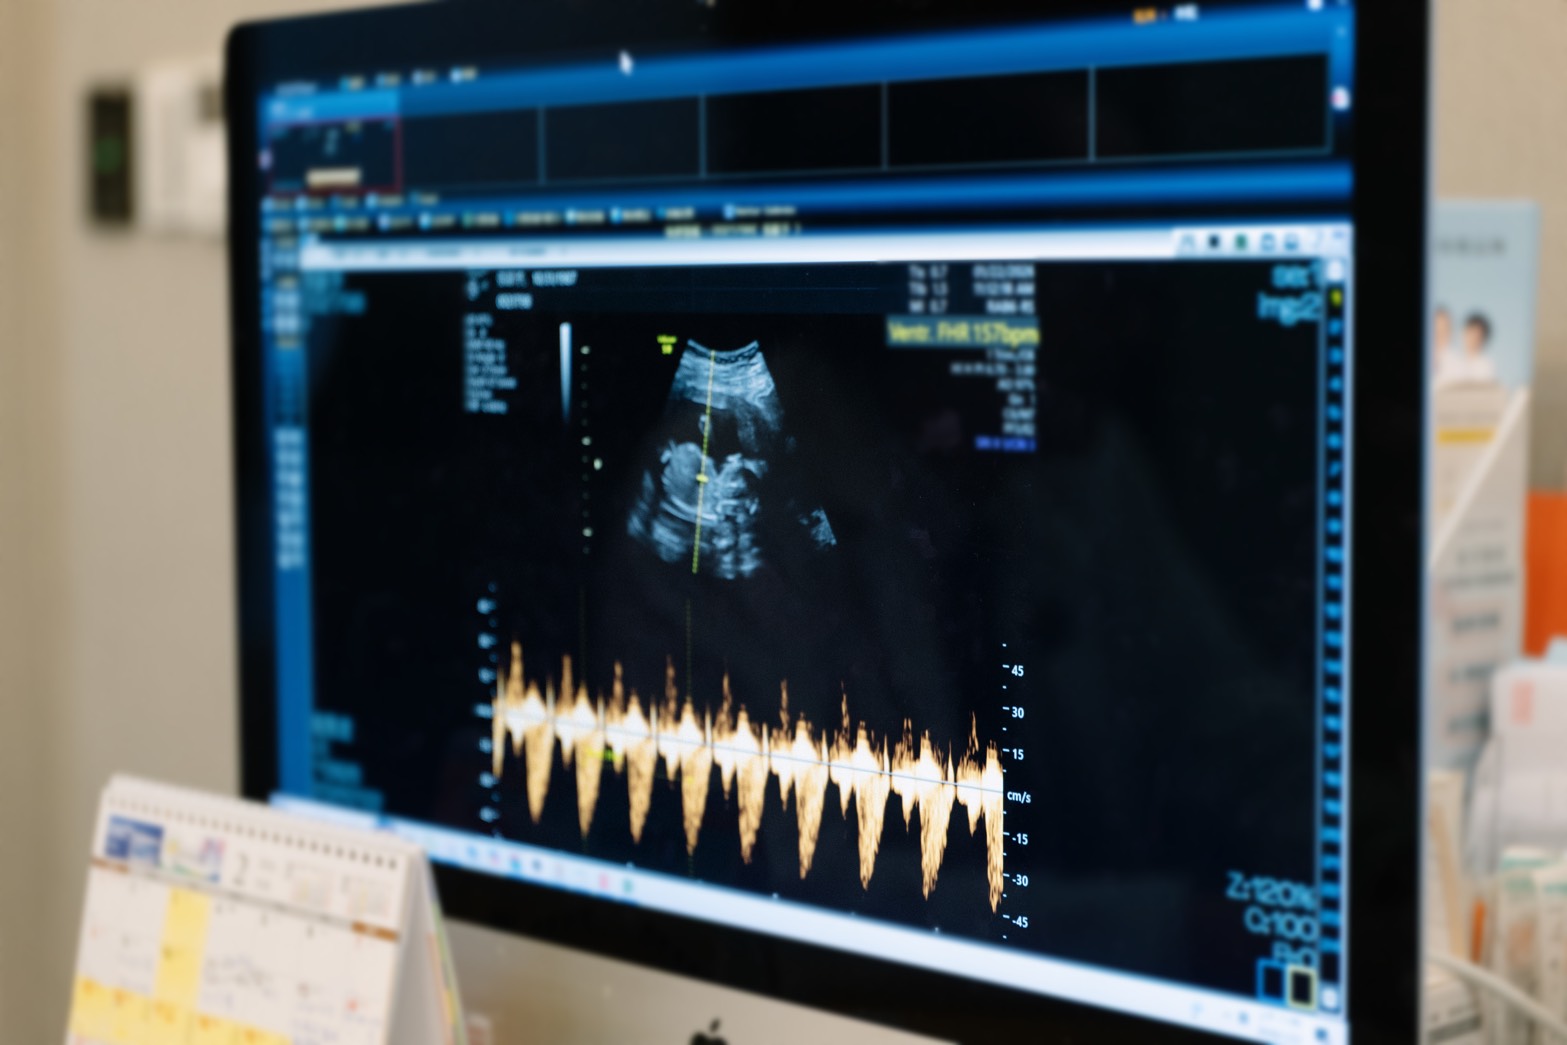

曾啟瑞醫師說明,PGS(胚胎植入前染色體篩檢)是在胚胎植入前,透過切片技術檢測其染色體是否正常,過程僅選取未來發育為胎盤的「滋養層」細胞,不會傷及發育為胎兒的「內細胞群」,好像從一顆樹的許多樹根中取樣。儘管PGS為目前臨床最先進的篩檢技術,但仍有 20% 的機率可能存在微小瑕疵或不著床,這是目前全球醫學無法完全排除的限制。

因此,臨床上會在基於既有條件,進一步釐清可能影響懷孕結果的原因;為使張齡予能夠成功懷孕,除了透過PGS篩選胚胎外,又再安排子宮內膜容受性檢測,精確定位出子宮內膜最適合受孕的時間點,在匯集成功三要素「好的胚胎,在對的時間,住進健康的子宮」後,幫助張齡予成功在第二次植入時順利受孕,圓了二寶夢。

由於長子「小班長」出生後患有先天性水腎,讓張齡予對二寶的健康格外重視。曾啟瑞醫師特別安排「雙重防護線」,除了第一步先以PGS 篩檢正常胚胎,第二步則是於懷孕 11-12 週時進行非侵入性胎兒染色體檢測(NIPT),此時胎盤細胞大量進入母體血液,透過母血篩檢,精準度會比胚胎時期更高,能夠提供父母更安心的保障。